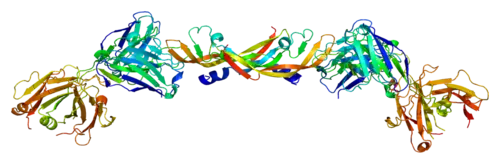

Vascular endothelial growth factor A (VEGF-A) is a protein that in humans is encoded by the VEGFA gene.[5]

This gene is a member of the platelet-derived growth factor (PDGF)/vascular endothelial growth factor (VEGF) family and encodes a protein that is often found as a disulfide linked homodimer. This protein is a glycosylated mitogen that specifically acts on endothelial cells and has various effects, including mediating increased vascular permeability, inducing angiogenesis, vasculogenesis, and endothelial cell growth, promoting cell migration, and inhibiting apoptosis. Alternatively spliced transcript variants, encoding either freely secreted or cell-associated isoforms, have been characterized.[6]

Vascular endothelial growth factor A (VEGF-A) is a dimeric glycoprotein that plays a significant role in neurons and is considered to be the main, dominant inducer of the growth of blood vessels. VEGFA is essential for adults during organ remodeling and diseases that involve blood vessels, for example, in wound healing, tumor angiogenesis, diabetic retinopathy, and age-related macular degeneration. During early vertebrate development, vasculogenesis occurs which means that the endothelial condense into the blood vessels. The differentiation of endothelial cells is dependent upon the expression of VEGFA and if the expression is abolished then it can result in the death of the embryo. VEGFA is produced by a group of three major isoforms as a result of alternative splicing and if any three isoforms are produced (VEGFA120, VEGFA164, and VEGFA188) then this will not result in vessel defects and death of the full VEGFA knockout in mice. VEGFA is essential in the role of neurons because they too need vascular supply and abolishing the expression of VEGFA from neural progenitors will result in defects of the brain vascularization and neuronal apoptosis. Anti-VEGFA therapy can be used to treat patients with undesirable angiogenesis and vascular leakage in cancer and eye diseases but also could result in the inhibition of neurogenesis and neuroprotection. VEGFA could be used to treat patients with neurodegenerative and neuropathic conditions and also increase vascular permeability which will stop the blood-brain barrier and increase inflammatory cell infiltration.[7][8][9]